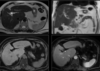

14

Q

Abdome: doença hepática difusa

V ou F?

As lesões focais hepáticas na imagem são suspeitas para metástases.

Sequências GRE em fase/fora de fase.

A

Falso.

As lesões na imagem correspondem a esteatose multifocal/multinodular.